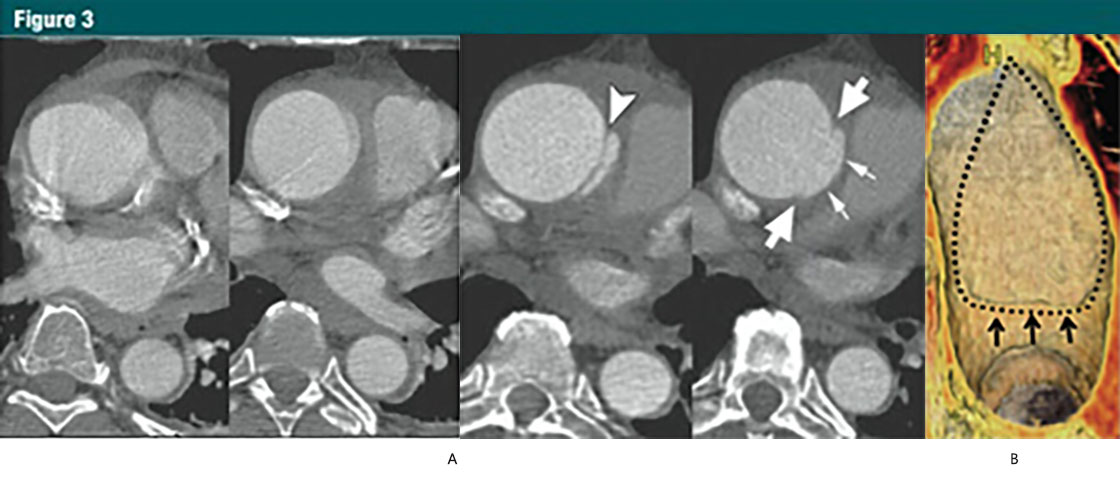

圖3 升主動(dòng)脈局限性內(nèi)膜撕裂

(A)上方:無(wú)心電門(mén)控的CTA顯示升主動(dòng)脈運(yùn)動(dòng)偽影,模糊;下方:12小時(shí)后,心電門(mén)控 CTA示:升主動(dòng)脈近端內(nèi)膜皮瓣(箭頭),伴隨一個(gè)侵蝕邊緣的局限性內(nèi)膜撕裂。局限性內(nèi)膜撕裂的邊緣(大箭頭)和主動(dòng)脈壁破壞形成的突起(小箭頭)清晰可見(jiàn)。這些微妙細(xì)節(jié)如果沒(méi)有使用心電門(mén)控是不可見(jiàn)的。

(B)VR重建顯示腔內(nèi)一側(cè)6cm長(zhǎng)的損傷。一個(gè)小的破損皮瓣(細(xì)箭)代表撕裂的起始端,并一直延伸到主動(dòng)脈弓的近端。虛線,代表撕裂的邊緣。(轉(zhuǎn)載,許可,引用24。)

少數(shù)有中層病變的患者,出現(xiàn)表淺或者部分撕裂(相當(dāng)于原發(fā)性內(nèi)膜撕裂),但并沒(méi)有形成一個(gè)單獨(dú)的流出道,或者造成壁內(nèi)血液的存留。這些少見(jiàn)的病變稱之為局限撕裂或者局限性?shī)A層,與典型夾層對(duì)比往往具有細(xì)微的影像改變(30,33,36)(圖3)。

In a small number of patients with medial disease, a superficial/partial thickness tear develops (the equivalent of a primary intimal tear) without the development ofa separate flow channel or accumulation of intramural blood. These rare lesionsare referred to as limited tears or limited dissection and tend to have subtle imaging findings when compared with classic dissection (30,33,36)(Fig 3).